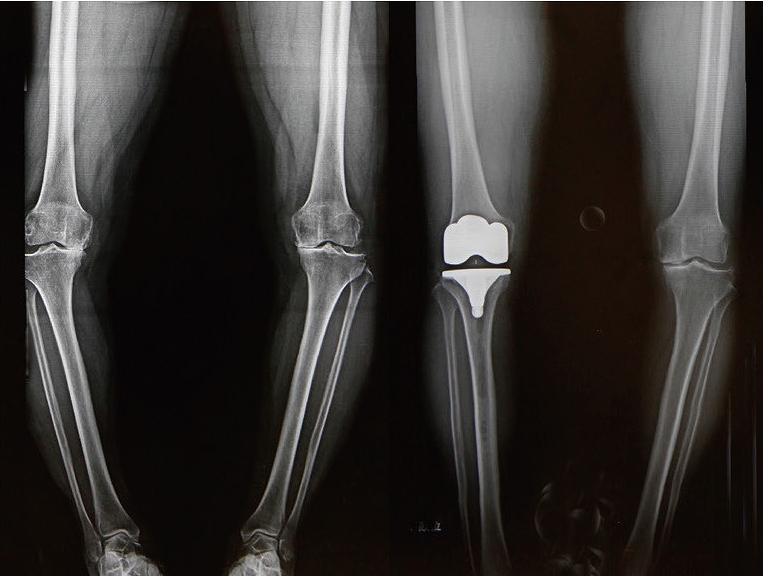

人工膝関節置換術

手術前と手術後のレントゲン

人工膝関節置換術は、変形性膝関節症や関節リウマチなどによって傷んだ膝関節の表面を、人工の関節部品(インプラント)に置き換える手術です。痛みの軽減や歩行能力の改善を目的として行われます。

手術では、大腿骨や脛骨(必要に応じて膝蓋骨)の骨の表面を整え、金属やポリエチレンなどでできた人工関節を設置し、骨セメントなどを用いて固定します。これにより、関節の動きをなめらかにし、日常生活動作の改善を目指します。

また、当院で近年、症例数が増加しているUKA(単顆置換術)は、TKA(全置換術)と比較して、置換が必要な部分のみに手術範囲を限定できるという特徴があります。そのため、相対的に骨の温存性が高く、前十字靱帯をはじめとする靭帯や健常な関節面を残すことが可能です。これにより手術侵襲が抑えられ、術後の違和感が少なく、早期の機能回復が得られやすいとされています。

実際に、無作為比較試験や国内外の臨床報告において、UKA(単顆置換術)はTKA(全置換術)と比較して、術後6週間から3か月にかけて、歩行能力などの日常生活動作に関連する回復が早く、術後疼痛の軽減や入院期間の短縮が期待できる手術法であることが示されています。

一方で、UKAは一般的にTKAと比べて手術視野が限られ、健常な骨や靭帯を温存しながら関節のバランスを精密に調整する必要があるため、より高い手術精度が求められる術式でもあります。

当院ではこうした特性を踏まえ、Makoロボット支援手術システムを導入し、術前の3D計画に基づいた骨切除およびインプラント設置の精度と再現性の向上に取り組んでいます。これにより、患者さん一人ひとりの膝の形態に即した、より正確で再現性の高いUKA手術を行うことが可能となっています。